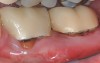

The workshop's group on periodontal soft-tissue root coverage procedures evaluated the predictability of root coverage procedures for single- and multiple-tooth Miller Class I and II10 periodontal recession defects. The workshop concluded that predictable root coverage was possible for Miller Class I and II recession involving a single tooth. When compared with the use of acellular dermal matrix graft (ADMG) (donor tissue) or EMD (porcine origin), procedures using a subepithelial connective tissue graft (SCTG) harvested from the patient's palate provided the best root coverage outcomes in conjunction with a coronally advanced flap.11 As alternatives to autogenous donor tissue, the workshop found strong evidence to support the use of an ADMG or EMD in conjunction with a coronally advanced flap and limited evidence to support the use of platelet-derived growth factor and xenogeneic collagen matrix.11 In addition, root coverage procedures were found to be effective for Miller Class I and II recession defects affecting multiple teeth, although the evidence is limited.11 Figure 1 and Figure 2 show the pretreatment and 1-year postoperative views of a soft-tissue root coverage treatment with SCTG and EMD that used a coronally advanced flap and a tunneling procedure. Figure 3 and Figure 4 depict the pretreatment and 3-year postoperative views of a root coverage procedure with ADMG and EMD that used a coronally advanced flap and a tunneling procedure (this patient was noncompliant following surgery and did not return to the office until the 3-year postoperative appointment).

(2.) Postoperative view after one year following treatment with SCTG (harvested from palate) and EMD using a coronally advanced flap and a tunneling procedure.

Figure 2